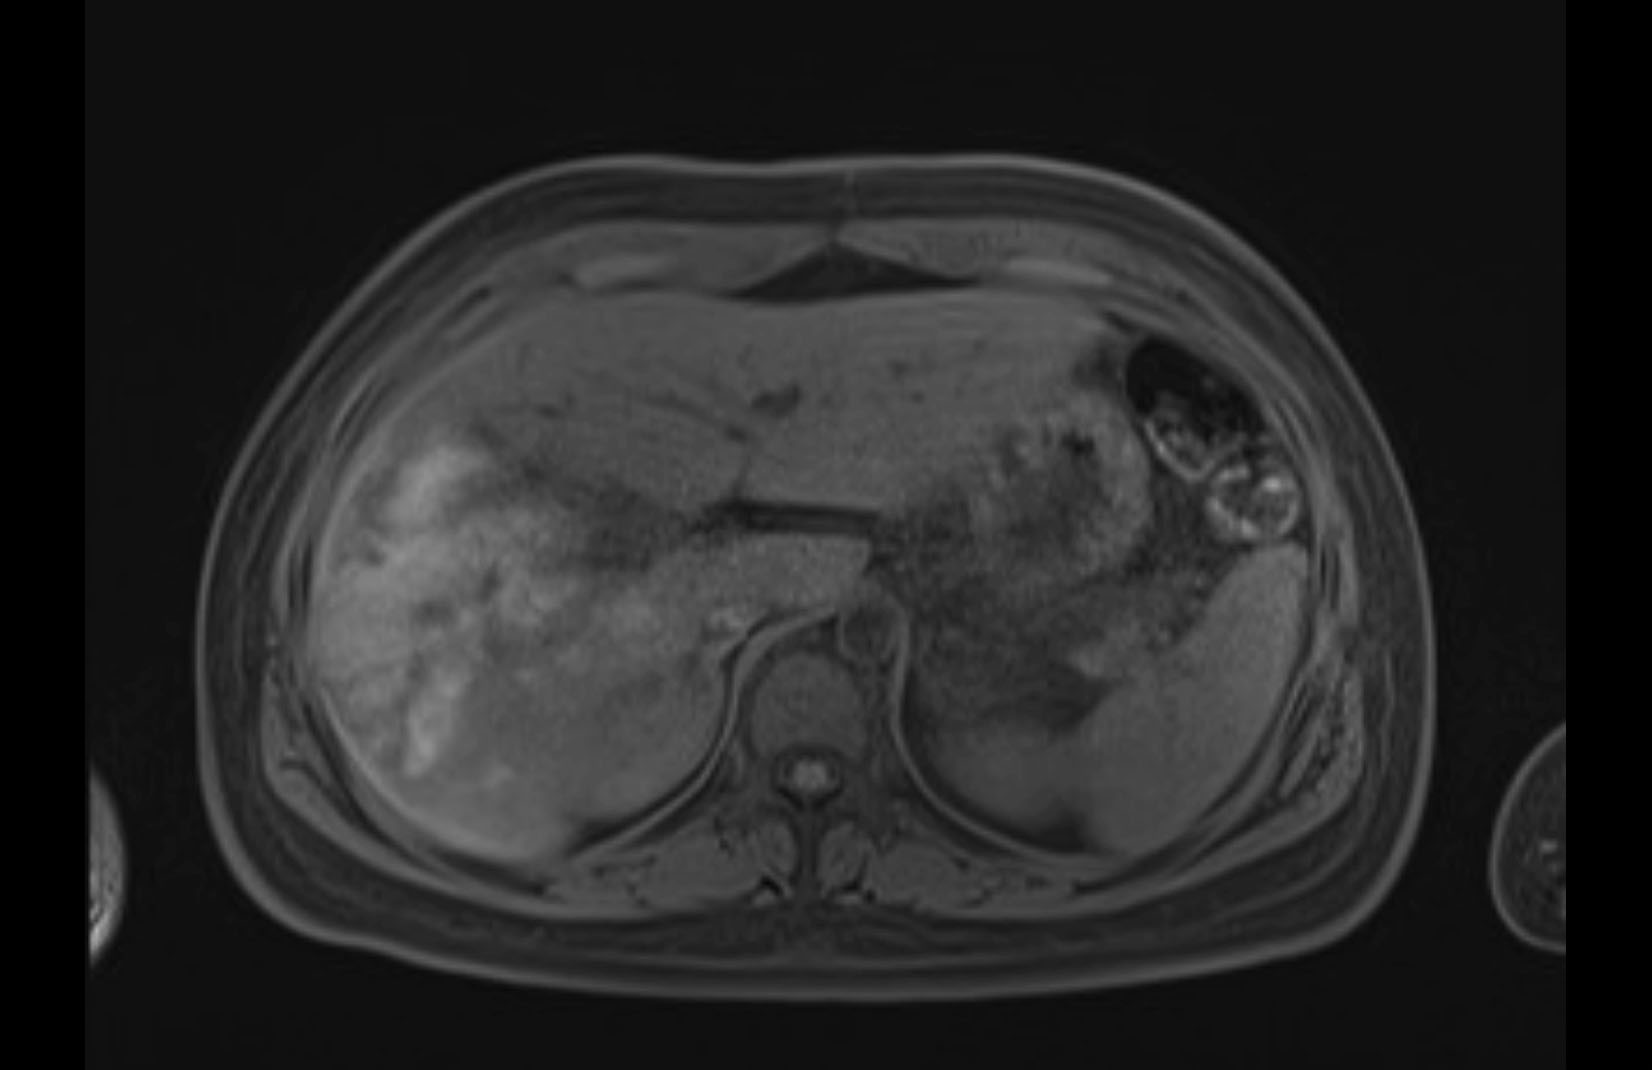

Imaging Analysis

Look through the patient's CT scan to identify any areas of concern for the necessary procedure.

MRI T1

MRI T2

Based on initial findings, which issue(s) would you be most concerned about?